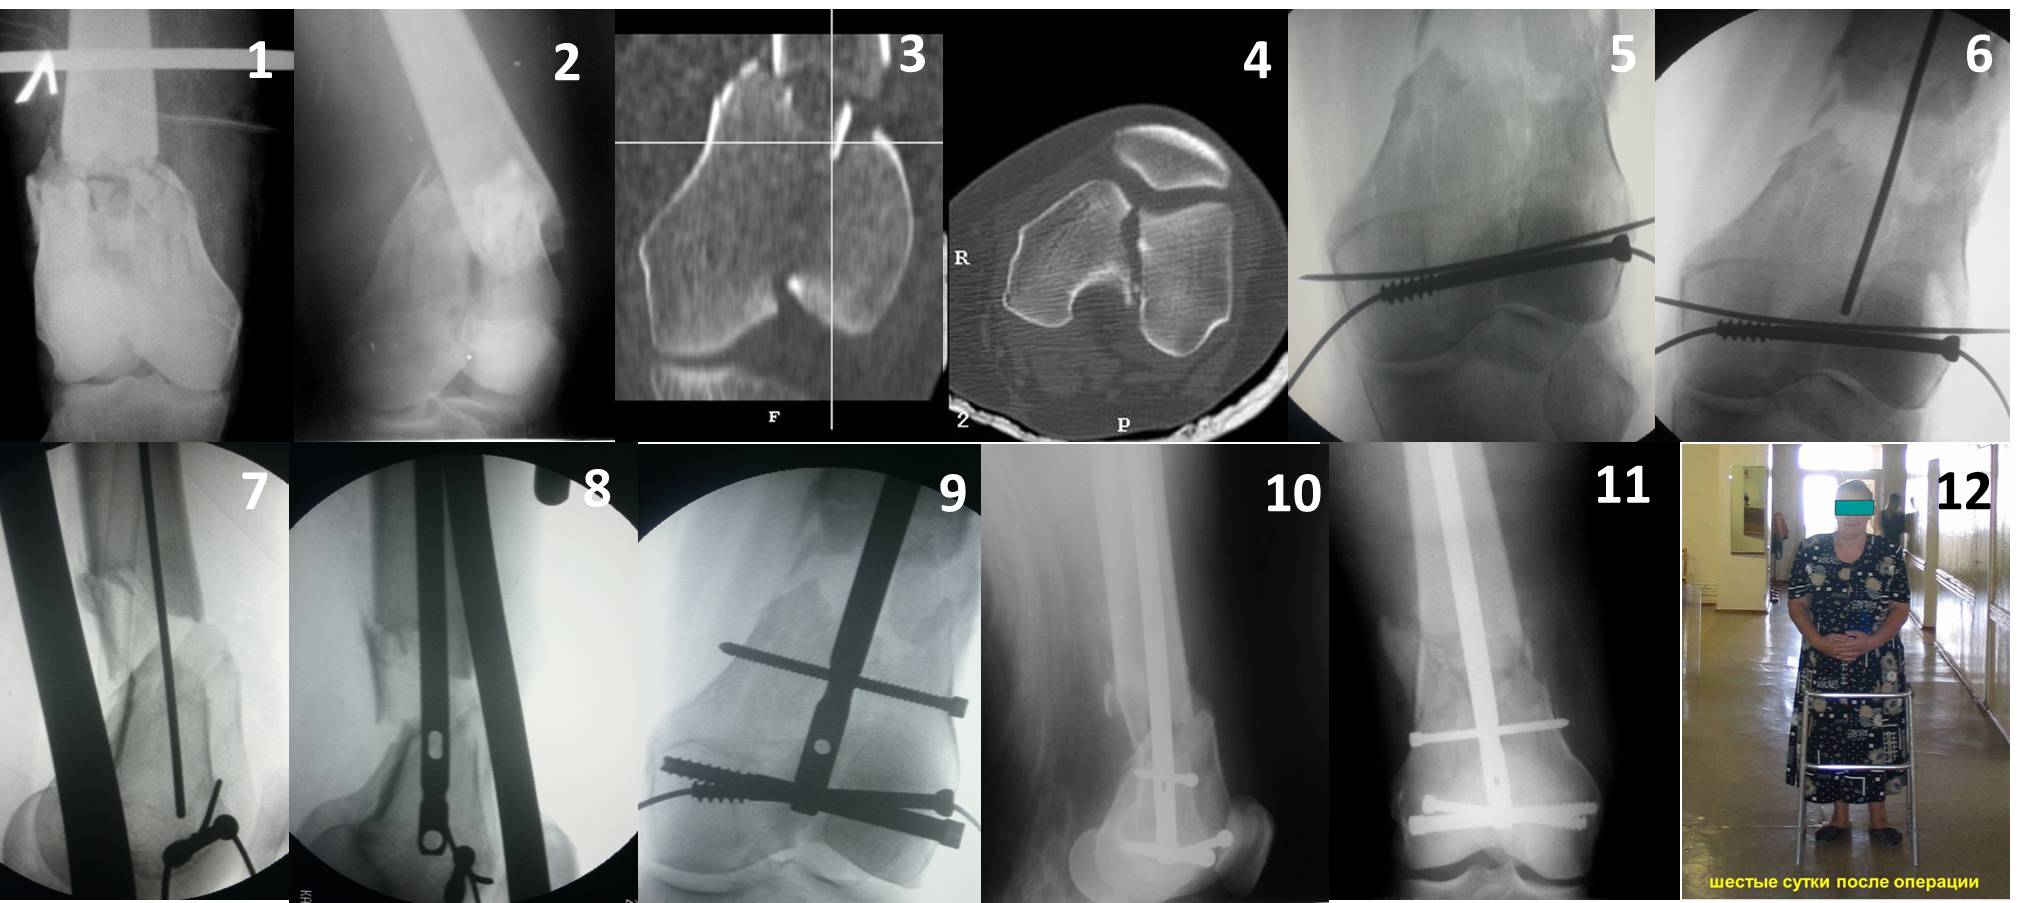

Здесь пример медиальной пластины и латеральный комбинированный метод (у второго больного старый перелом тибиал плато, леченный где то и когда то)

Ответ на эту часть Вашего поста – вложенный файл. Больная оперирована неделю назад по поводу открытого перелома дистального эпиметафиза бедренной кости. После операции она идёт в рентгенкабинет для выполнения послеоперационной контрольной рентгенографии, представленной на слайдах 10 и 11. Узнав, почему её фотографируют, просила передать Вам, Антон, привет.

В приложении пример недавней операции, C3, открытая репозиция, фиксация мыщелков спицами и винтами, ретроградный синтез большеберцовым гвоздем 10,5 мм диаметром, винты 5 мм.

По прямому снимку репозиция удалось, поздравляю! А с латеральной стороны подозрение на флексионный компонент латерального мыщелка остается, а снимок получился косым, надо было бы повторить.

Выбор имплантов не совсем удачный, подкожно выступающие болты в мыщелках вскоре могут привести к проблемам. Вместо солитарной фиксации болтом-стяжкой дистально можно было бы добавить пару винтов, которые создали бы ротационную стабильность и межфрагментарную компрессию.

Возможно, есть скрытый замысел, неочевидный для нас - не понятны латерально оставленные спицы. Спицы возможный очаг вторичного осложнения, и, тем более у взрослых, тонкие спицы не создают адекватную фиксацию.